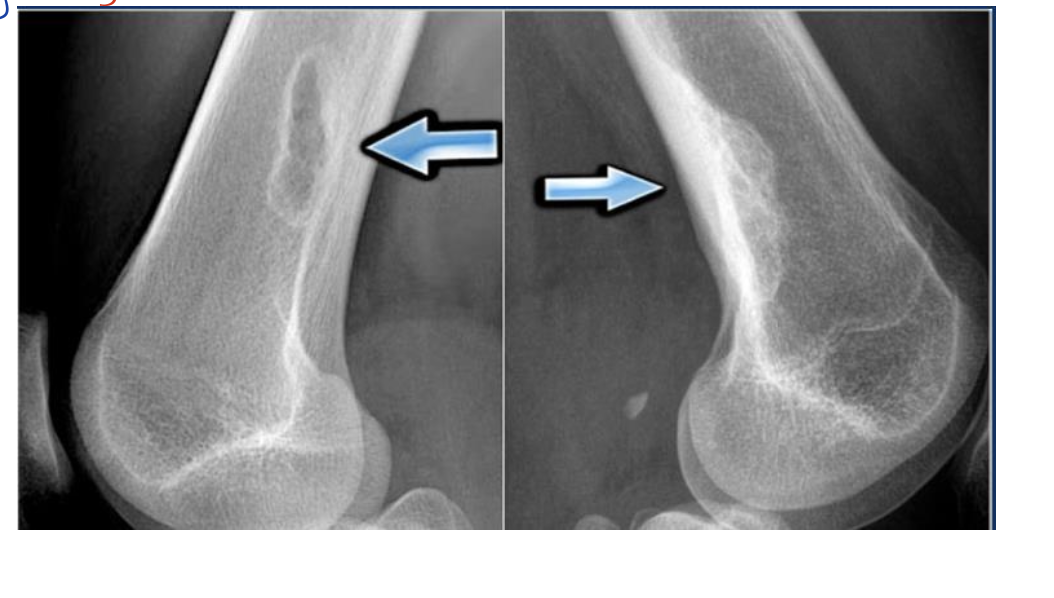

type of fracture ?

SAY everything